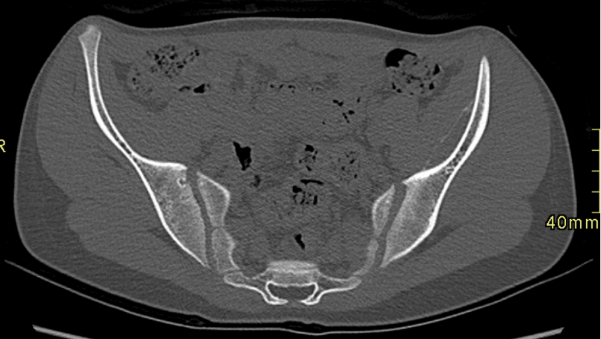

Cortes axiales de TC de pelvis, en ventana de partes blandas (Imagen 6) y ósea (Imagen 7). Lesión lentiforme subperióstica iliaca izquierda, con calcificación periférica.

Corte axial en ventana ósea de TC de pelvis (Imagen 8). Asimetría en la rama ilio-pubiana del cartílago trirradiado, con mayor amplitud a izquierda.

Colección hemática entre el periostio y la cortical, generalmente post traumática. Se presenta como una lesión lentiforme adosada al hueso, con niveles líquido-líquido en RM y sin realce significativo tras contraste. Puede asociarse a calcificación periférica en TC. Los hallazgos descritos y el antecedente clínico son concordantes con este diagnóstico.